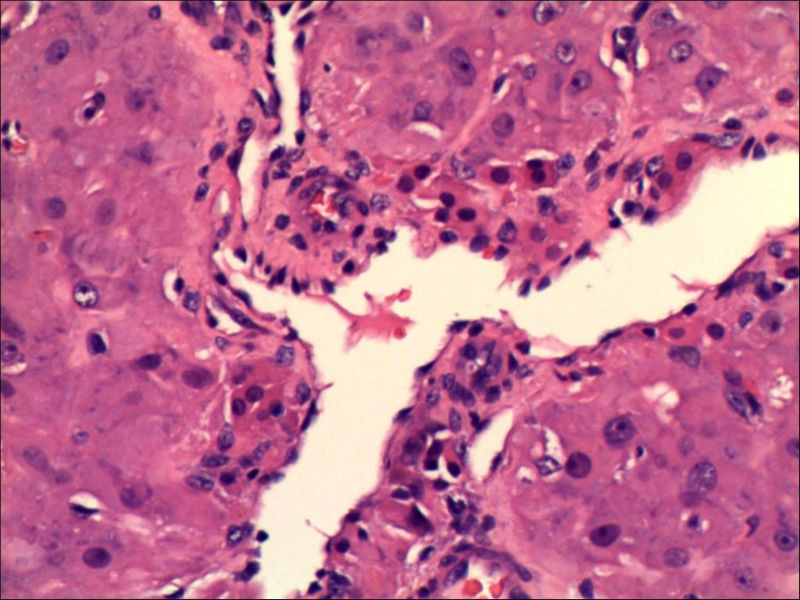

女,27岁,送检右侧卵巢肿物(另外还送检左侧卵巢肿物,大体及镜下显示为畸胎瘤),卵圆形,大小2×1×1cm,似有包膜。卵巢肿物图1

卵巢畸胎瘤中正常卵巢的黄体组织,铺砖样排列,胞浆宽大,较典型。

不好意思,可能是我没说清楚,患者对侧卵巢是畸胎瘤,不是同一侧的,我初步考虑门细胞瘤,图21,22,24,25,26中央的一些细胞是不是很像门细胞

谢谢大家的回答和解疑,忘记一个重要的病史,就是该女性为产妇。但是妊娠黄体瘤与类固醇细胞瘤怎么鉴别呢

那应该是妊娠黄体/黄体瘤,类固醇细胞瘤有嗜酸细胞和组织细胞样细胞两种,此例显然不是。